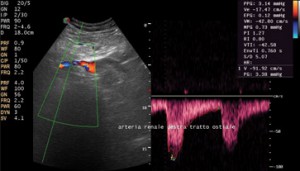

L’ecocardiogramma è una tecnica che si basa sull’impiego di ultrasuoni e consente di vedere dall’interno sia le pareti del cuore sia le sue strutture interne (come le valvole) e di valutare esattamente la contrattilità del cuore globale.